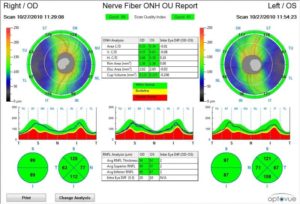

OCT..the diagnostic tool for diseases of retina

Optical coherence tomography (OCT) is a non-invasive imaging test. OCT uses light waves to take cross-section pictures of your retina.

With OCT, your ophthalmologist can see each of the retina’s distinctive layers. This allows your ophthalmologist to map and measure their thickness. These measurements help with diagnosis. They also provide treatment guidance for glaucoma and diseases of the retina. These retinal diseases include age-related macular degeneration (AMD) and diabetic eye disease,vascular occlusions as discussed above.

What happens during OCT?

To prepare you for an OCT exam, your ophthalmologist may or may not put dilating eye drops in your eyes. These drops widen your pupil and make it easier to examine the retina.

You will sit in front of the OCT machine and rest your head on a support to keep it motionless. The equipment will then scan your eye without touching it. Scanning takes about 5 – 10 minutes. If your eyes were dilated, they may be sensitive to light for several hours after the exam.